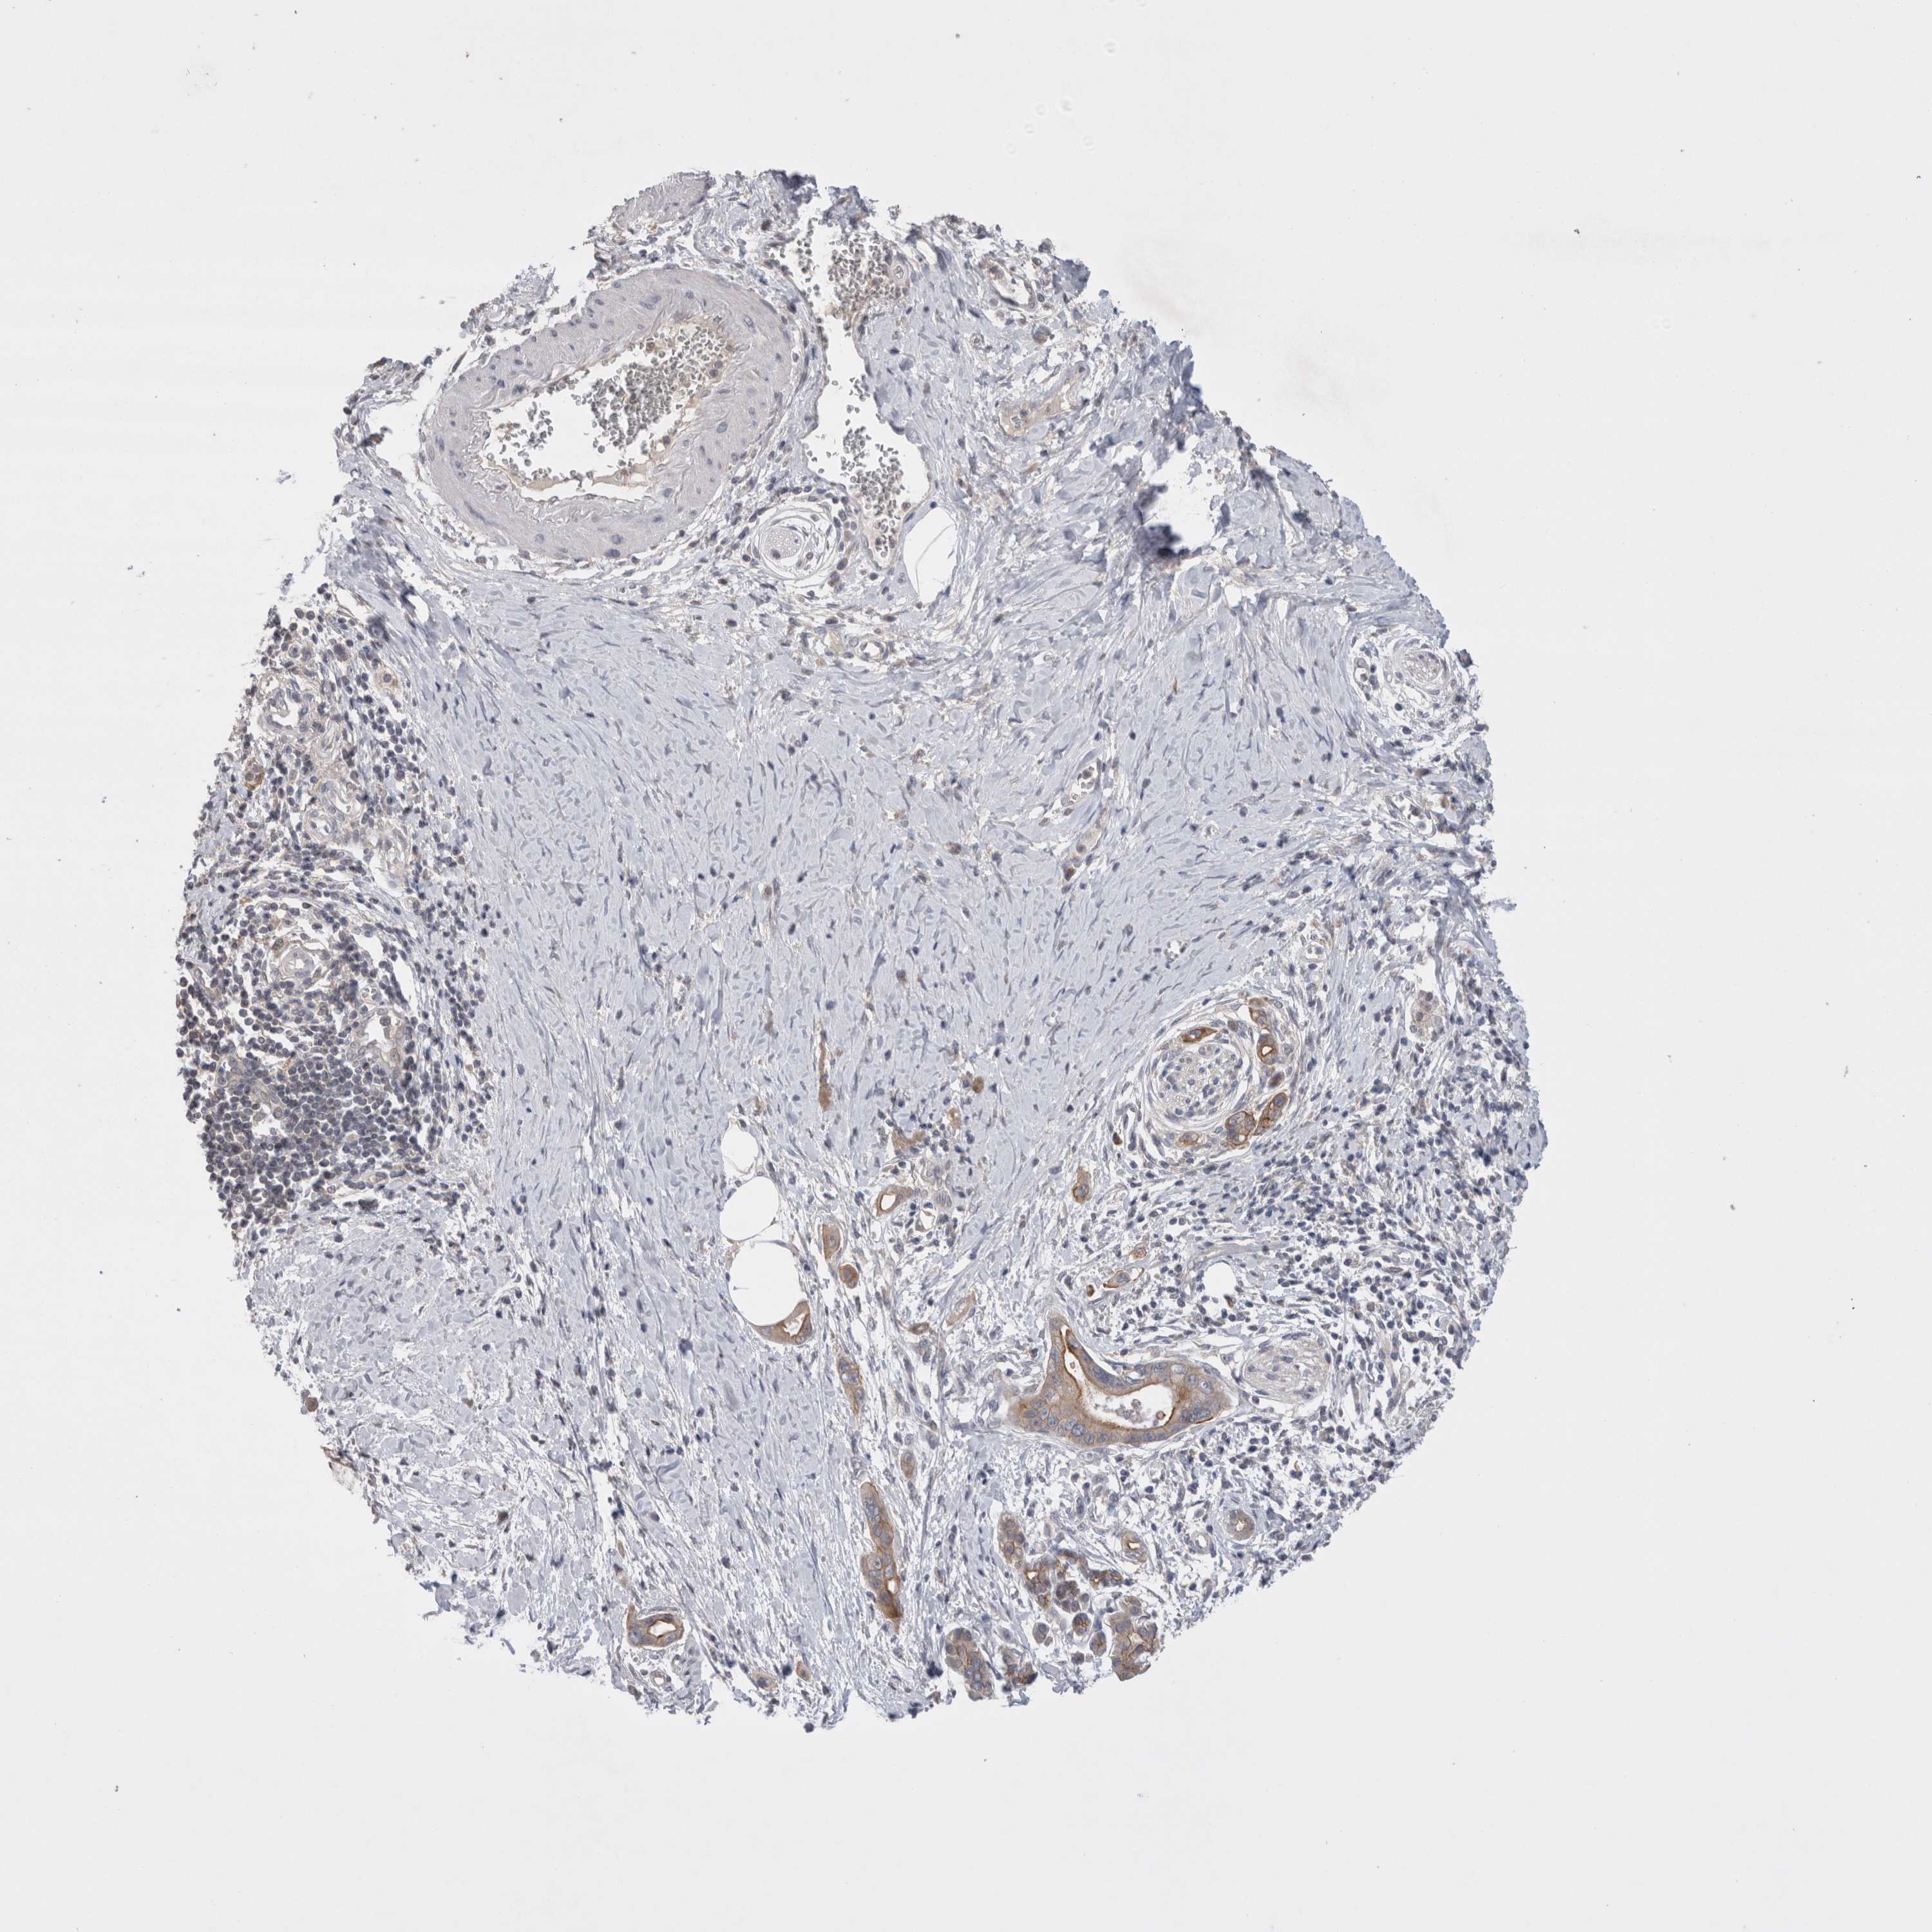

PANCREATIC CANCER - Protein expressioni

A mouse-over function shows sample information and annotation data. Click on an image to view it in a full screen mode. Samples can be filtered based on level of antibody staining by selecting one or several of the following categories: high, medium, low and not detected. The assay and annotation is described here.

Note that samples used for immunohistochemistry by the Human Protein Atlas do not correspond to samples in the TCGA dataset.

Antibody stainingi

Antibody staining in the annotated cell types in the current human tissue is reported as not detected, low, medium, or high, based on conventional immunohistochemistry profiling in selected tissues. This score is based on the combination of the staining intensity and fraction of stained cells.

Each image is clickable and will lead to virtual microscopy that enables deeper exploration of all samples and also displays staining intensity scores, fraction scores and subcellular localization as well as patient and tissue information for each sample.

Antibody HPA024335

Staining

High

Medium

Low

Not detected

Intensity

Strong

Moderate

Weak

Negative

Quantity

>75%

75%-25%

<25%

None

Location

Nuclear

Cytoplasmic/membranous

Cytoplasmic/membranous,nuclear

Adenocarcinoma, NOS